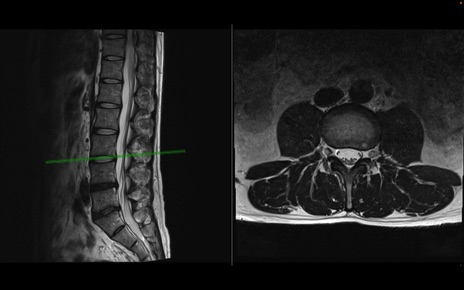

【症例】40歳代男性

【主訴】左臀部〜大腿後面痛み

【現病歴】2週間前から腰痛あり。2日前に夜中にくしゃみをした際に激痛が出現。疼痛強いため来院。

【身体所見】左臀部〜大腿後面、下腿後面のしびれ。SLR -/+ 30度、うつ伏せ困難、筋力低下なし。

異常所見と診断は?